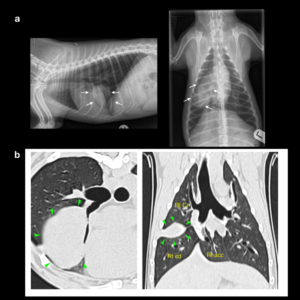

X-rays are usually the first way of assessing whether or not a dog has lung cancer. More information can be gained from Computed Tomograpy (CT) scans which give us much more detail which helps with treatment planning. The scans are very useful for detecting what part of the lung is affected and also whether or not any secondary tumours are present. These scans are usually performed under general anaesthesia. The final diagnosis ie what type of lung cancer can only be made after a biopsy is taken either before or during surgery.

Figure1. Chest x-rays, lung mass in right middle lung lobe (white arrows). CT scan, lung mass in right middle lung lobe (green arrowhead)